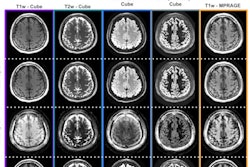

Niendorf described the benefits of 7-tesla MRI, such as increased signal-to-noise ratio, higher spatial resolution, and the ability to produce more detailed images, citing examples in relation to multiple sclerosis (MS).

"We believe 7T MRI can really make a difference when it comes to the differentiation of MS lesions from other neurodegenerative diseases (such as Susac syndrome)," he said.